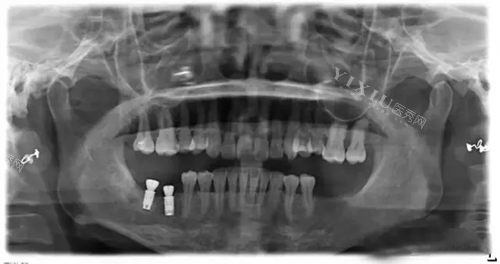

韩国美格真种植体X光片.webp

韩国美格真种植牙植入图